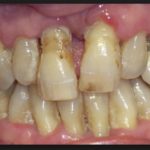

Стоматологи выделяют три степени протекания болезни. На первой и самой легкой стадии образуется карман в десне глубиной до 4 мм. Пока ощущения неприятные, но терпимые. Изменения в костной ткани еще не начались. Средняя степень тяжести характеризуется увеличением глубины кармана до 6 мм. Такой периодонтит симптомы имеет более явные: корни зубов слегка оголяются, десны воспалены, зубы становятся подвижными. Тяжелая стадия – это карман глубиной уже до 9 мм, сильное нагноение. Зубы меняют свое положение, а их подвижность настолько сильная, что не позволяет нормально питаться.

Хронический периодонтит зуба боли практически не вызывает, если речь идет о фиброзной форме. Только по рентгену можно диагностировать недуг. Ощущается тяжесть, подвижность пораженных зубов, их оттенок может меняться. Бывает так, что человек живет много лет с хронической формой и не подозревает об этом, поскольку визуального осмотра порой недостаточно для постановки диагноза. При обострении симптомы такие же, как при острой стадии

Гранулематозный периодонтит приводит к образованию гранулемы, но этот процесс не отмечается явными симптомами. Хотя люди могут отмечать подвижность зубов, изменение их оттенка или боли при приеме пищи. Также может выпасть ранее установленная пломба. Если киста при росте смещается в сторону, при пальпации чувствуется набухание десны, небольшое уплотнение в пораженной области.